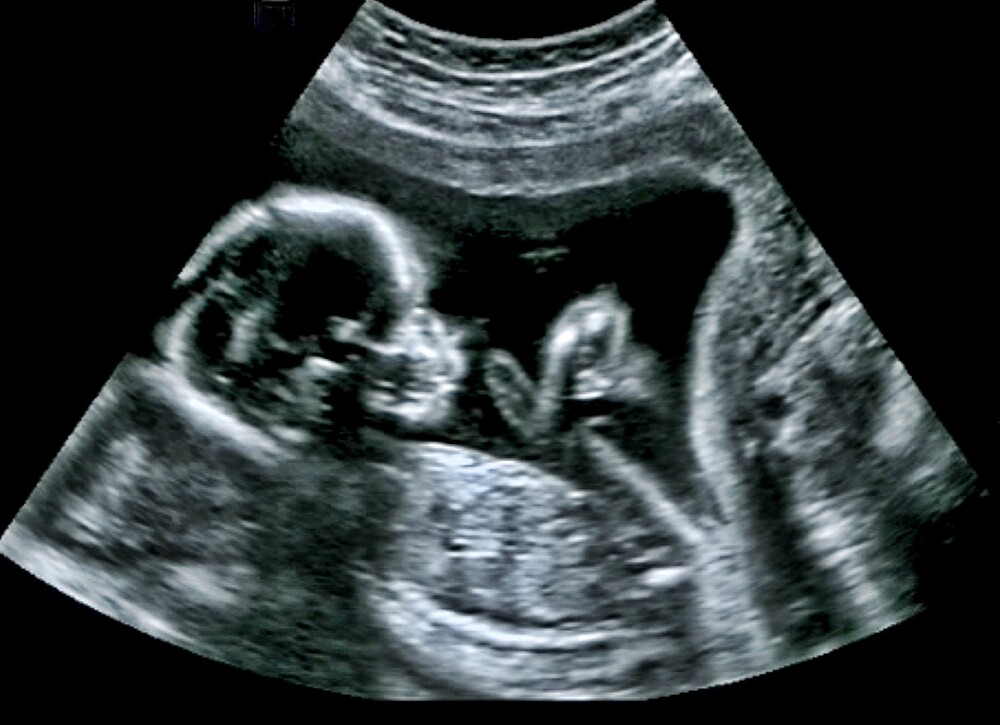

At the very beginning of your pregnancy, your doctor will measure your baby’s crown-rump length, or SSL, during the ultrasound examinations to determine his or her size. Between the 7th and 13th week of pregnancy, the crown-rump length is the distance between the highest point of your baby’s head and breech. But why doesn’t the doctor measure your baby’s total length? This is because of the curved position of the fetus at this stage of development, which makes it impossible to measure it in its entirety.

By measuring the crown-rump length, your gynaecologist determines the age of your baby from the time of fertilisation. This method is very accurate in the first weeks of pregnancy, as all foetuses develop in the same way at the beginning of a pregnancy. From about the 7th week of pregnancy, your baby will grow about one millimetre a day. But do not worry if your offspring is a little smaller or larger than the norm. After all, the moment of fertilisation cannot be determined to the minute. If you notice anything unusual about your baby, your doctor will inform you.